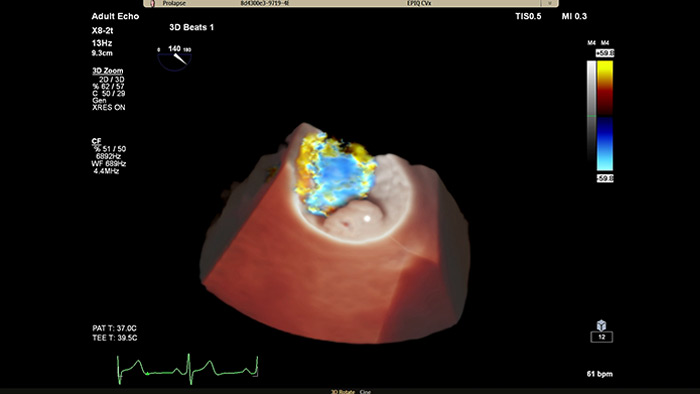

View enhanced visualizations of structures and flow with TrueVue Color